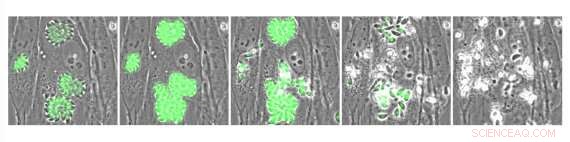

Intracellular Toxoplasma parasites expressing the genetically encoded calcium indicator GCaMP. Parasites were treated with A23187, a compound that causes influx of calcium and stimulates parasite egress. Credit: Whitehead Institute for Biomedical Research

One potential approach to treat infection could be drugs that disrupt the parasites' calcium signaling, which they rely on to spread from cell to cell in their hosts. The parasites need an influx of calcium in order to burst out of an infected host cell—a process called egress—and move through the host's body and invade other cells. In previous work, a researcher from Whitehead Institute Member Sebastian Lourido's lab, Saima Sidik, had tested a large collection of molecules and identified one called enhancer 1 (ENH1), which perturbed the parasites' calcium levels and prevented egress, as a promising anti-parasitic lead. However, the original experiments did not determine how ENH1 acts. In research published in the journal ACS Chemical Biology on June 29, Alice Herneisen, a graduate student in Lourido's lab, and Lourido, who is also an assistant professor of biology at the Massachusetts Institute of Technology, used an approach called thermal proteome profiling to discover how ENH1 prevents T. gondii parasites from egress. They identified the main target of ENH1 as a calcium-dependent molecule called CDPK1 that parasites use to prepare for egress, moving between cells, and invasion of host cells. ENH1 binds to and prevents CDPK1 from functioning.